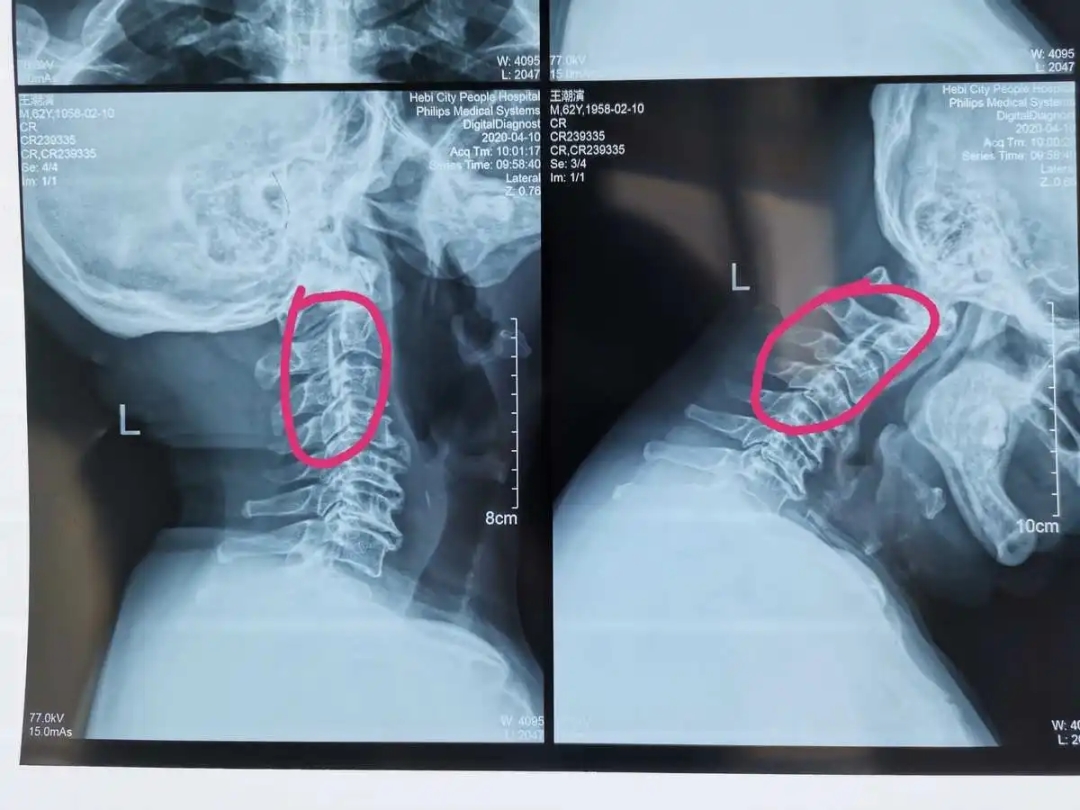

- 颈椎曲度变直和颈椎反弓

表现为颈部后方的不舒,多是因为长时间低头写字和低头玩手机导致

![]()